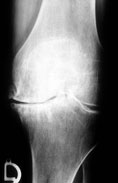

Arthrose Röntgenbild eines "Arthrose" Kniegelenkes mit starker Knorpelabnutzung und Gelenkspaltverschmälerung.